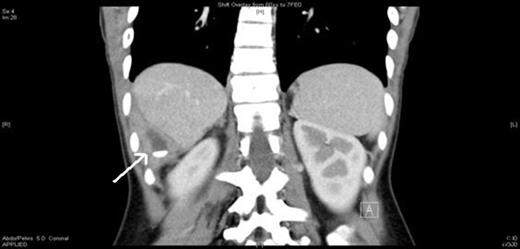

Computed tomography of the abdomen was performed and revealed a 4×3cm structure of low attenuation posterolateral to segment 6 of the liver with surrounding irregular wall and a central 15 mm high density lesion, suggestive of a peritoneal foreign body, possibly a retained appendicolith from previous surgery (Figure 1).

Abdominal CT scan showing a radio-opaque faecolith in the right upper quadrant (arrowed)